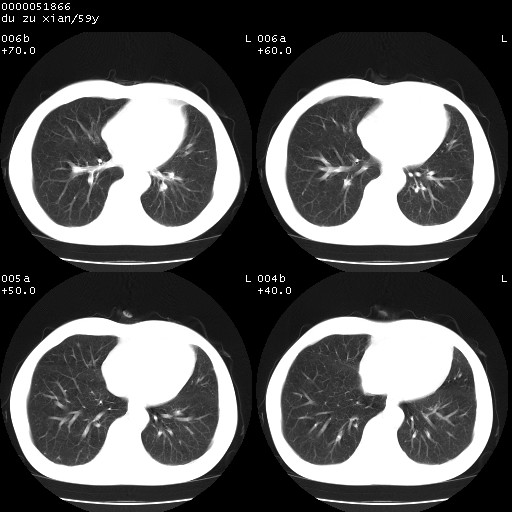

以下是引用宇宙ct在2008-8-25 23:21:00的发言:[br]右肺周围性肺癌并肋骨转移,纵隔淋巴结转移。

以下是引用zsl6918在2008-8-25 22:40:00的发言:[br]右肺周围性肺癌并肋骨转移,纵隔淋巴结转移。

以下是引用zy_zj在2008-8-26 15:24:00的发言:[br]单从病变本身,我倾向良性炎性病变,但肋骨转移了,所以说是考虑右肺周围性肺癌并肋骨、纵隔淋巴结转移可能性大。